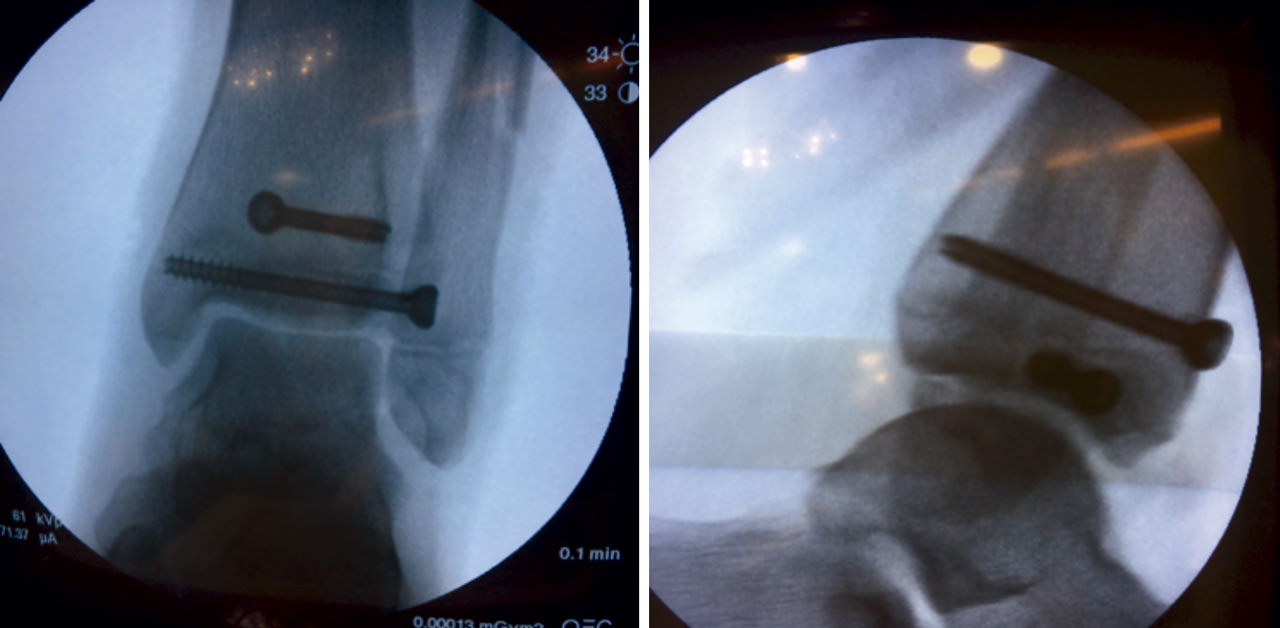

Por ello, realizamos reducción abierta mediante abordaje anterior ligeramente lateral: incisión recta de aproximadamente 8 cm, seccionando el retináculo extensor y rechazando a medial el tendón del músculo tibial anterior y extensor hallucis longus y hacia lateral el paquete vasculonervioso (vena y arteria dorsal del pie y nervio peroneo profundo). Apertura de la cápsula articular para obtener un mejor acceso a la zona articular y fisaria, donde procedimos a la colocación de agujas de Kirschner para ayudar a mantener la reducción de la fractura (Figura 4).

Tras conseguir una adecuada reducción de la fractura, realizamos fijación interna con 2 tornillos canulados de rosca parcial de 16 mm (un tornillo epifisario de lateral a medial y otro metafisario anteroposterior) comprobando bajo fluoroscopio la reducción de la fractura (Figura 5).

Figura 4. Reducción abierta, fijación temporal con agujas de Kirschner.

Figura 5. Control radiológico intraoperatorio: fijación con tornillos canulados.